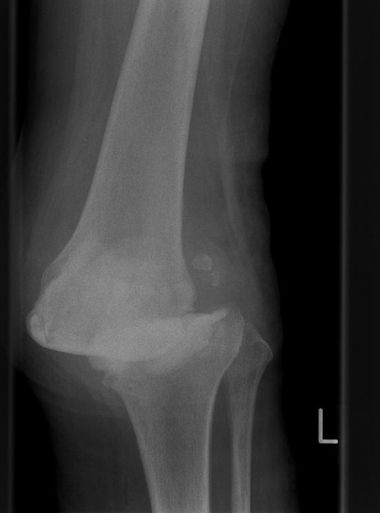

81-jährige Patientin mit innenseitiger Arthrose des linken Kniegelenks. Wir implantierten eine Schlittenprothese. Die Patientin demonstrierte im März 2021 ein gutes Gangbild mit nahezu freier Kniegelenksbeweglichkeit.

OXFORDSCHLITTEN

innenseitige Kniegelenksarthrose

OP Planung

Nach der OP (Oxfordschlitten)